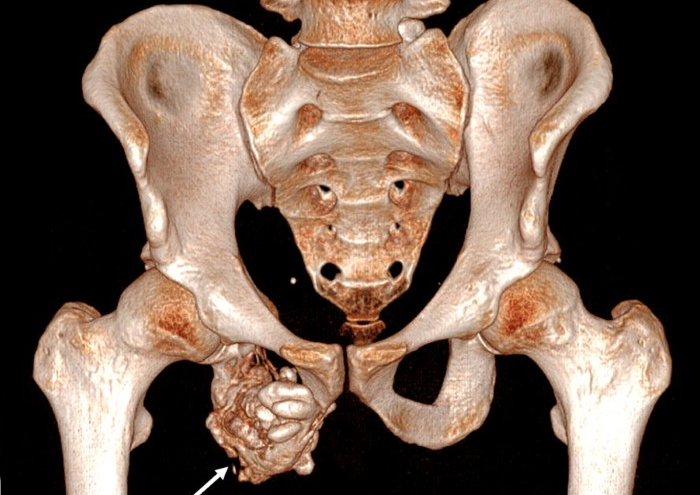

کوردوما (Chordoma)

کوردوما توموری نادر است که از باقیماندههای نوتوچورد منشا میگیرد و اغلب در استخوان ساکروم لگن ظاهر میشود. این تومور رشد کند اما تهاجمی محلی دارد و متاستاز دیر ایجاد میشود. علامت اصلی، درد مزمن و گاهی علائم عصبی ناشی از فشار روی اعصاب است. درمان اصلی جراحی با حذف کامل تومور یا en bloc resection(برداشت یکپارچه تومور است)، چرا که موفقیت درمانی وابسته به حاشیه جراحی منفی است. پیچیدگی آناتومیک لگن، نزدیکی عروق و اعصاب و نیاز به بازسازی، چالش بزرگی در درمان ایجاد میکند.